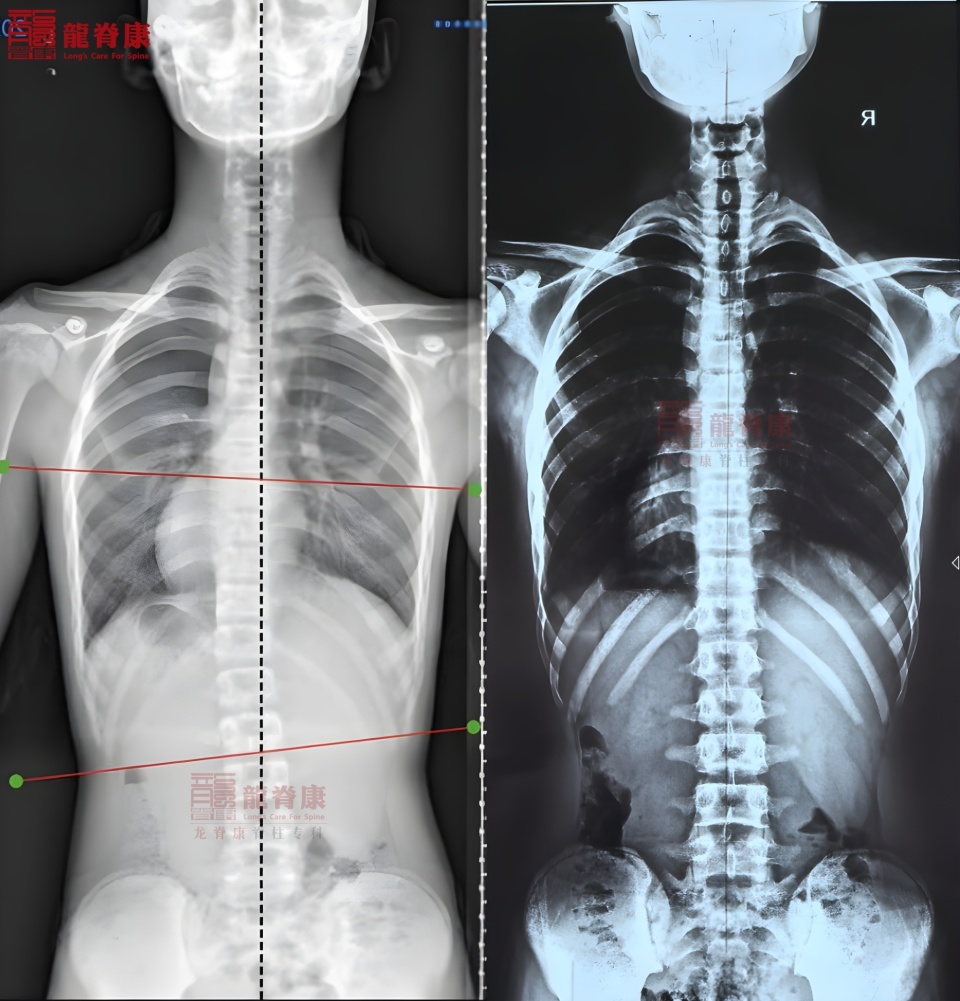

13岁的小W同学,2025年学校体检侧弯筛查提示异常,7月去外院拍片后确诊脊柱侧弯,Cobb角10°,处于侧弯临界值。家长发现孩子日常体态明显不对称,果断在龙脊康门诊启动运动康复训练,每日坚持20-30分钟针对性训练。

半年后复查,X光片未显示侧弯,体表对称,已不符合脊柱侧弯诊断标准,后续只需加强核心力量,侧弯复发风险极低。